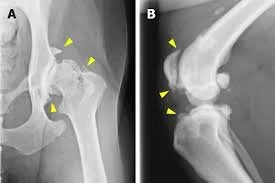

hip and knee arthitis

Arthritis is a degenerative joint disease that commonly affects older dogs.

Over time, the cartilage inside the joints wears down, causing inflammation and pain.

Hip dysplasia is a genetic condition in which the hip joint does not develop normally.

This abnormal joint structure leads to instability, inflammation, and eventually arthritis.

Large breed dogs are especially prone to hip dysplasia.